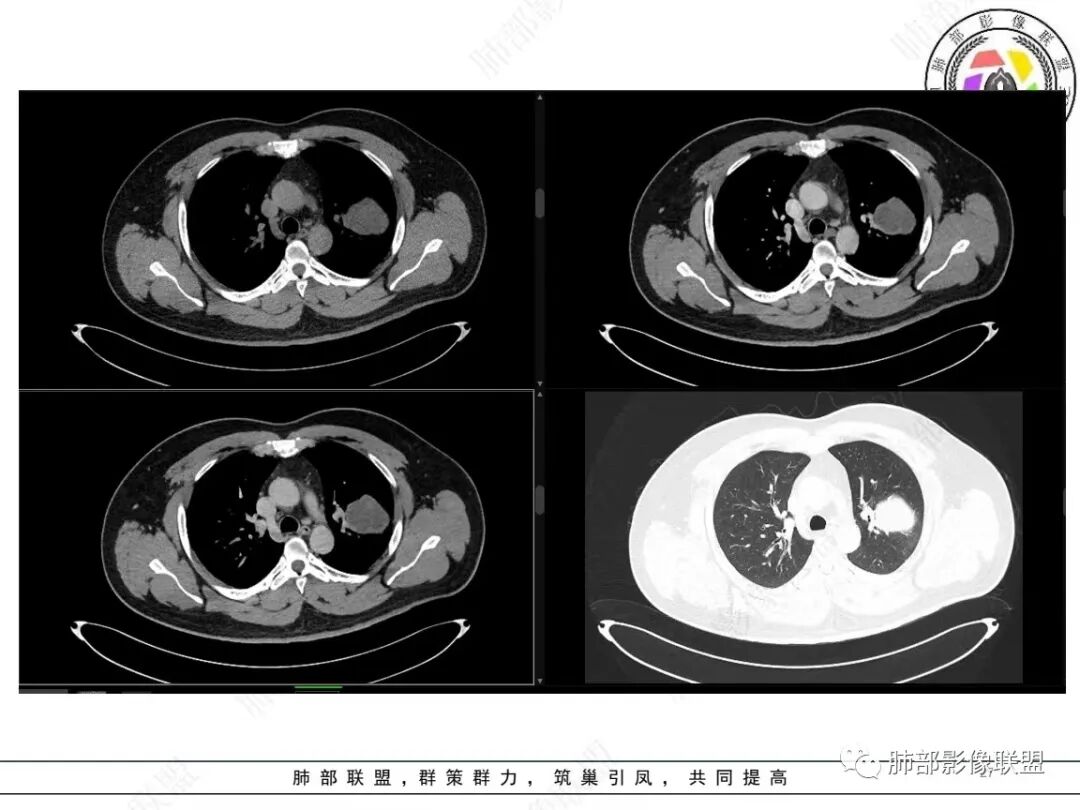

中年人,咳血,左肺上叶实性团块,边界清晰,与胸膜分界不清,可见栽赃表现,病灶推挤支气管及肺血管内移,增强可能条纹血管影,总体强化明显,考虑恶性或交界性肿瘤,间叶组织来源,肉瘤,SFT,肉瘤样癌,滑膜肉瘤。

左肺上叶胸膜肿块,浅分叶,边缘光整,密度不均匀,周围气管及血管受压推移,边缘强化,考虑肉瘤,鉴别SFT

左肺上叶占位,平扫密度较低,临近胸膜栽赃桩,外向内生长,边缘有膨隆、毛糙,增强后轻度强化,边缘弧线样强化,考虑肉瘤样癌

左上肺软组织肿块,周围散在磨玻璃影,界不清,窄基底贴于胸壁,胸膜下脂肪间隙不清,呈低强化,胸膜下见。与主病灶强化方式一样的病变,2R区见肿大淋巴。考虑恶性,间叶组织来源合并出血。

青年男性,咯血;CT示左肺上叶胸膜下软组织肿块,边界尚清,宽基底与胸膜相连,增强动脉期内见细条状血管影,轻度延迟强化,定位:肺外,胸膜外脂肪存在,考虑脏层胸膜起源;定性:考虑SFT。

影像表现:左肺上叶占位合并出血,胸膜栽赃,边缘强化,局部见血管影,中心密度20Hu,无强化,符合非液化坏死。定位:肺内,定性恶性(明显血管影,栽赃排除错构瘤,中心无强化排除PSP,无明显清楚的坏死边界,强化不符合肉芽肿,排除结核),年龄轻,无长时间吸烟史和肺气肿改变,肉瘤样癌可能性很小,与支气管无确切关系,所以病理类型考虑来源于肺间叶组织的肉瘤,骨外尤文?滑膜肉瘤?